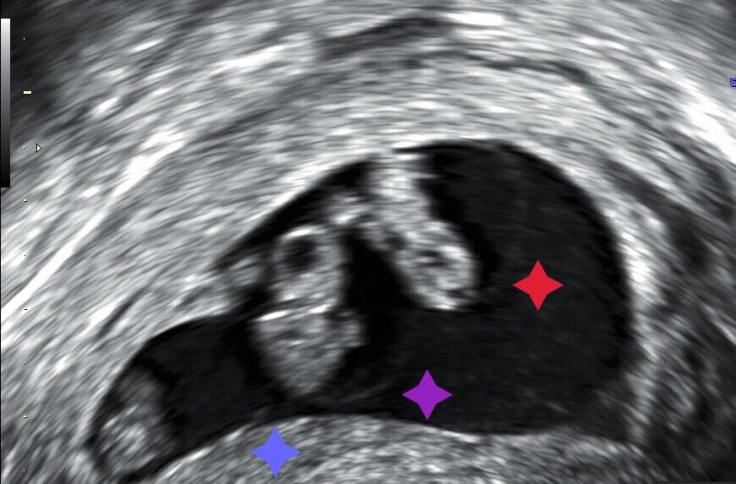

譬如這張圖片上的八週大小

此時三個羊膜清晰可見

這是單絨毛膜三羊膜三胞胎